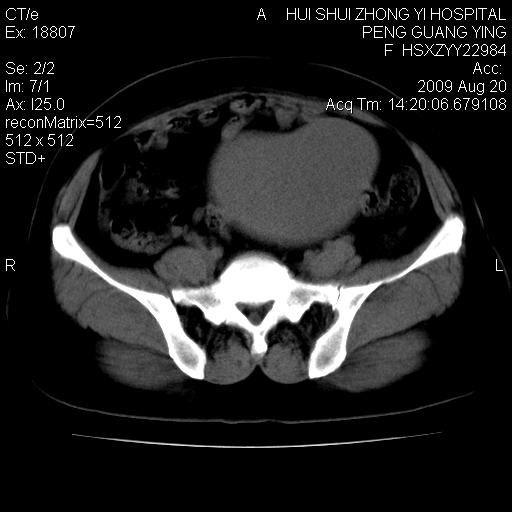

标题: CT21707:女,42岁,因发现下腹部包块2月。 [打印本页]

标题: CT21707:女,42岁,因发现下腹部包块2月。

目前的影像表现显示肿块位于腹腔及盆腔,但具体定位,分清来源较困难,是否来源于卵巢、子宫无法定论,子宫直肠及子宫膀胱周围脂肪间隙尚较清晰,如果患者有过腹腔好或者盆腔手术史,也可以形成不典型的血中,最好手术后定为定性,我期待结果。

考虑子宫肌瘤。

子宫肌瘤